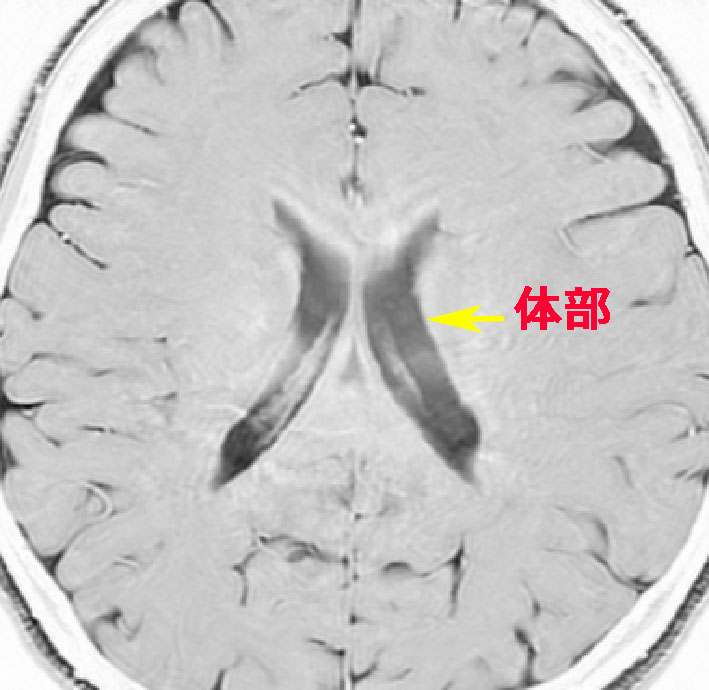

側脳室

水頭症です,側脳室体部がぷーっと膨らんで,中に髄液が大量にたまっています。

これは64歳男性の中脳水道閉塞症による閉塞性水頭症で,これでも無症状でした。